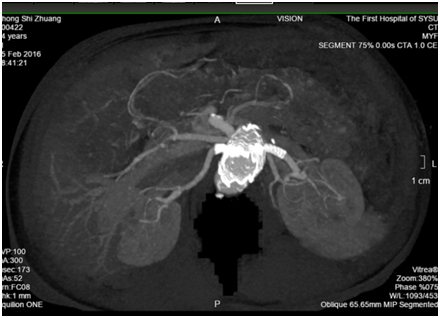

术后造影显示腹主动脉瘤完全隔绝,双侧肾动脉及肠系膜上动脉血流通畅,各脏器未见明显缺血,患者无腹痛,无肾功能损害,肌酐尿素氮未见升高。一星期后复查CTA显示支架位置良好,未见明显内漏,双肾动脉及肠系膜上动脉未见明显狭窄或闭塞。患者顺利康复出院。

术后1周复查CTA三维重建结果